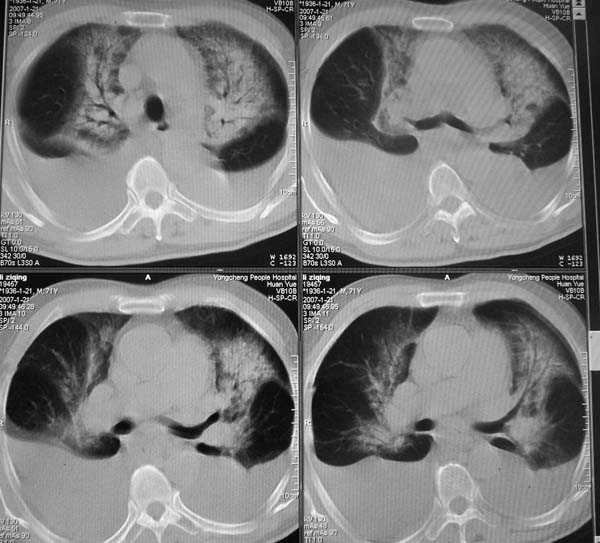

以下是引用zyx168在2007-1-21 17:08:00的发言:[br]男,71岁,咳嗽、胸闷10天余,咯血1天。[br]两肺大片状密度均匀影,充气支气管征象明显,左房增大,双侧胸腔内新月形液性密度影。[br]考虑:1,心源性肺水肿伴双侧胸腔中等量积液;[br] 2,两肺肺炎?